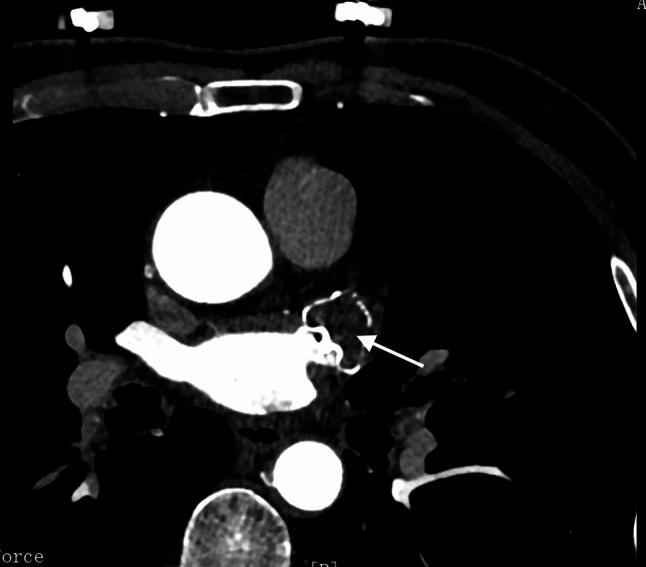

In this study, 68 AF patients who underwent successful implantation of the Watchman device without peri-device leak (PDL) during follow-up were included. The endothelialization status was assessed using Transesophageal echocardiography (TEE) and LAA computed tomography angiography (CTA) at 6 weeks and 6 months post-implantation. Adverse cerebro-cardiac events were documented at one-year follow-up. Baseline characteristics, including age, device sizes, and clinical indicators, were analyzed as potential predictors for IDE.

方法